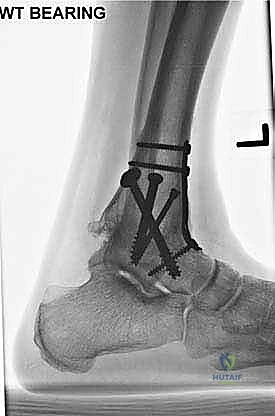

- الأشعة السينية أثناء الوقوف (Weight-bearing X-rays): هي الفحص الذهبي والأهم. يجب أن تؤخذ الأشعة والمريض واقف لتحمل الوزن. تظهر الأشعة تضيق المسافة المفصلية (دليل على فقدان الغضروف)، وجود نتوءات عظمية، تصلب العظم، وأي انحراف في محور المفصل.

لماذا المدخل الأمامي (Anterior Approach)؟

تاريخياً، تم وصف العديد من المداخل الجراحية لتثبيت الكاحل (المدخل الجانبي، المدخل الخلفي، المدخل عبر المناظير). ومع ذلك، يُفضل الأستاذ الدكتور محمد هطيف استخدام المدخل الجراحي الأمامي في حالات محددة ولأسباب علمية قوية:

- رؤية ممتازة للمفصل: يوفر المدخل الأمامي رؤية بانورامية واسعة ومباشرة لكامل السطح المفصلي للظنبوب وعظم الكاحل، مما يسمح بإزالة الغضاريف التالفة بدقة متناهية.

- تصحيح التشوهات بدقة: يسمح هذا المدخل بتعديل انحرافات الكاحل (سواء كان يميل للداخل Varus أو للخارج Valgus) وإعادته إلى المحور الميكانيكي الطبيعي للساق.

- الحفاظ على عظم الشظية (Fibula): على عكس المدخل الجانبي الذي يتطلب غالباً قطع عظم الشظية، يحافظ المدخل الأمامي على الشظية سليمة، مما يحافظ على العرض الطبيعي للكاحل ويحمي الأربطة الجانبية.

- تثبيت ميكانيكي حيوي أقوى: يتيح المدخل الأمامي وضع شريحة معدنية (Anterior Plate) على الجانب الأمامي للمفصل. من الناحية الميكانيكية الحيوية (Biomechanics)، يعتبر الجانب الأمامي هو "جانب الشد" (Tension side) أثناء المشي. وضع الشريحة هنا يوفر تثبيتاً فائق القوة ويقلل من معدلات عدم الالتئام.

- تجنب الأعصاب والأوعية الدموية الرئيسية: رغم وجود الحزمة الوعائية العصبية الأمامية (الشريان الظنبوبي الأمامي والعصب الشظوي العميق)، إلا أن الجراح المتمرس مثل الدكتور هطيف يقوم بعزلها وحمايتها بدقة تامة.